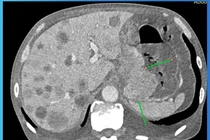

Bà Liên được kiểm tra sức khỏe tổng quát, các chỉ số tim mạch, huyết áp đều bình thường. Tiếp tục nội soi dạ dày không đau bằng máy nội soi có độ phóng đại 150 lần, bác sĩ phát hiện có dị vật như một cuống trái cây bắt ngang qua dạ dày.

Hình ảnh nội soi cho thấy, dị vật đâm xuyên ngang thành dạ dày (hình trái), dị vật dài 4 cm được nội soi gắp ra ngoài (hình phải) - Ảnh BVCC

Ngay trong lúc nội soi, bác sĩ sử dụng kẹp, rút dị vật đưa ra ngoài an toàn. Sau 30 phút hồi tỉnh, bà Liên không có còn triệu chứng đau, được về nhà trong ngày.